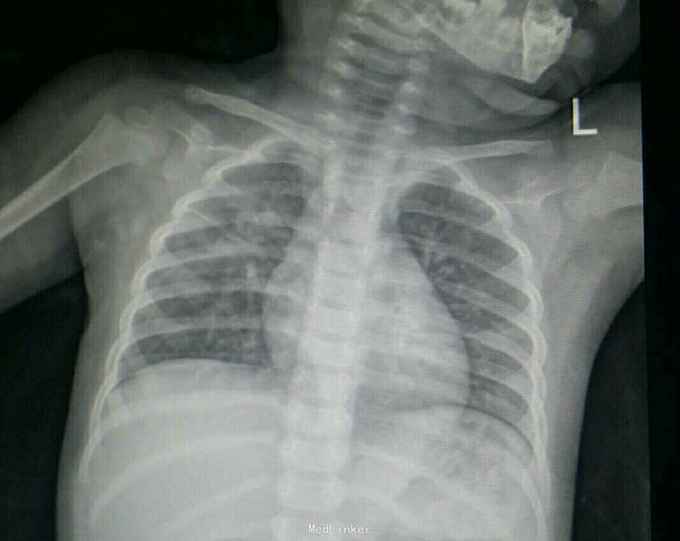

大叶性肺炎一例

患儿,男,4岁,咳嗽三天,不爱活动1天。

胸片,CT.如图,最后一图为一周后复查胸片。